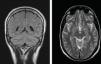

A los 11 días en planta presenta alteración visual con ceguera cortical a la exploración. El TC de cráneo muestra edema vasogénico posterior occipital (predominio izquierdo). Presenta crisis comiciales iniciándose tratamiento con valproato y se solicita RMN cráneo observándose imágenes compatibles con síndrome de PRES (áreas focales múltiples y confluentes hiperintensas en T2, iso-relativamente hipointensas en T1, sin traducción en difusión, preferentemente subcotico-yuxtacorticales afectando de forma simétrica a regiones parieto-occipitales posteriores, temporo-occipitales infero-laterales, frontales superior-medias y hemisféricas cerebelosas posteriores, y traduciendo la presencia de edema vasogénico) (fig. 1). En planta destaca hipertensión arterial con cifras de hasta 160mmHg de sistólica y 100mmHg de diastólica, ya presente previo al alta de UCI, y la persistencia del fracaso renal precisando hemodiálisis intermitente.

Los hallazgos radiológicos son necesarios para el diagnóstico. Incluyen áreas de edema vasogénico de predominio en la zona parieto-occipital y afectación de sustancia blanca profunda y estructuras infra-tentoriales. Se ha descrito la incidencia de regiones afectadas, siendo un 98,7% en zona parieto-occipital, 78,9% frontal posterior y 68,4% temporal5.